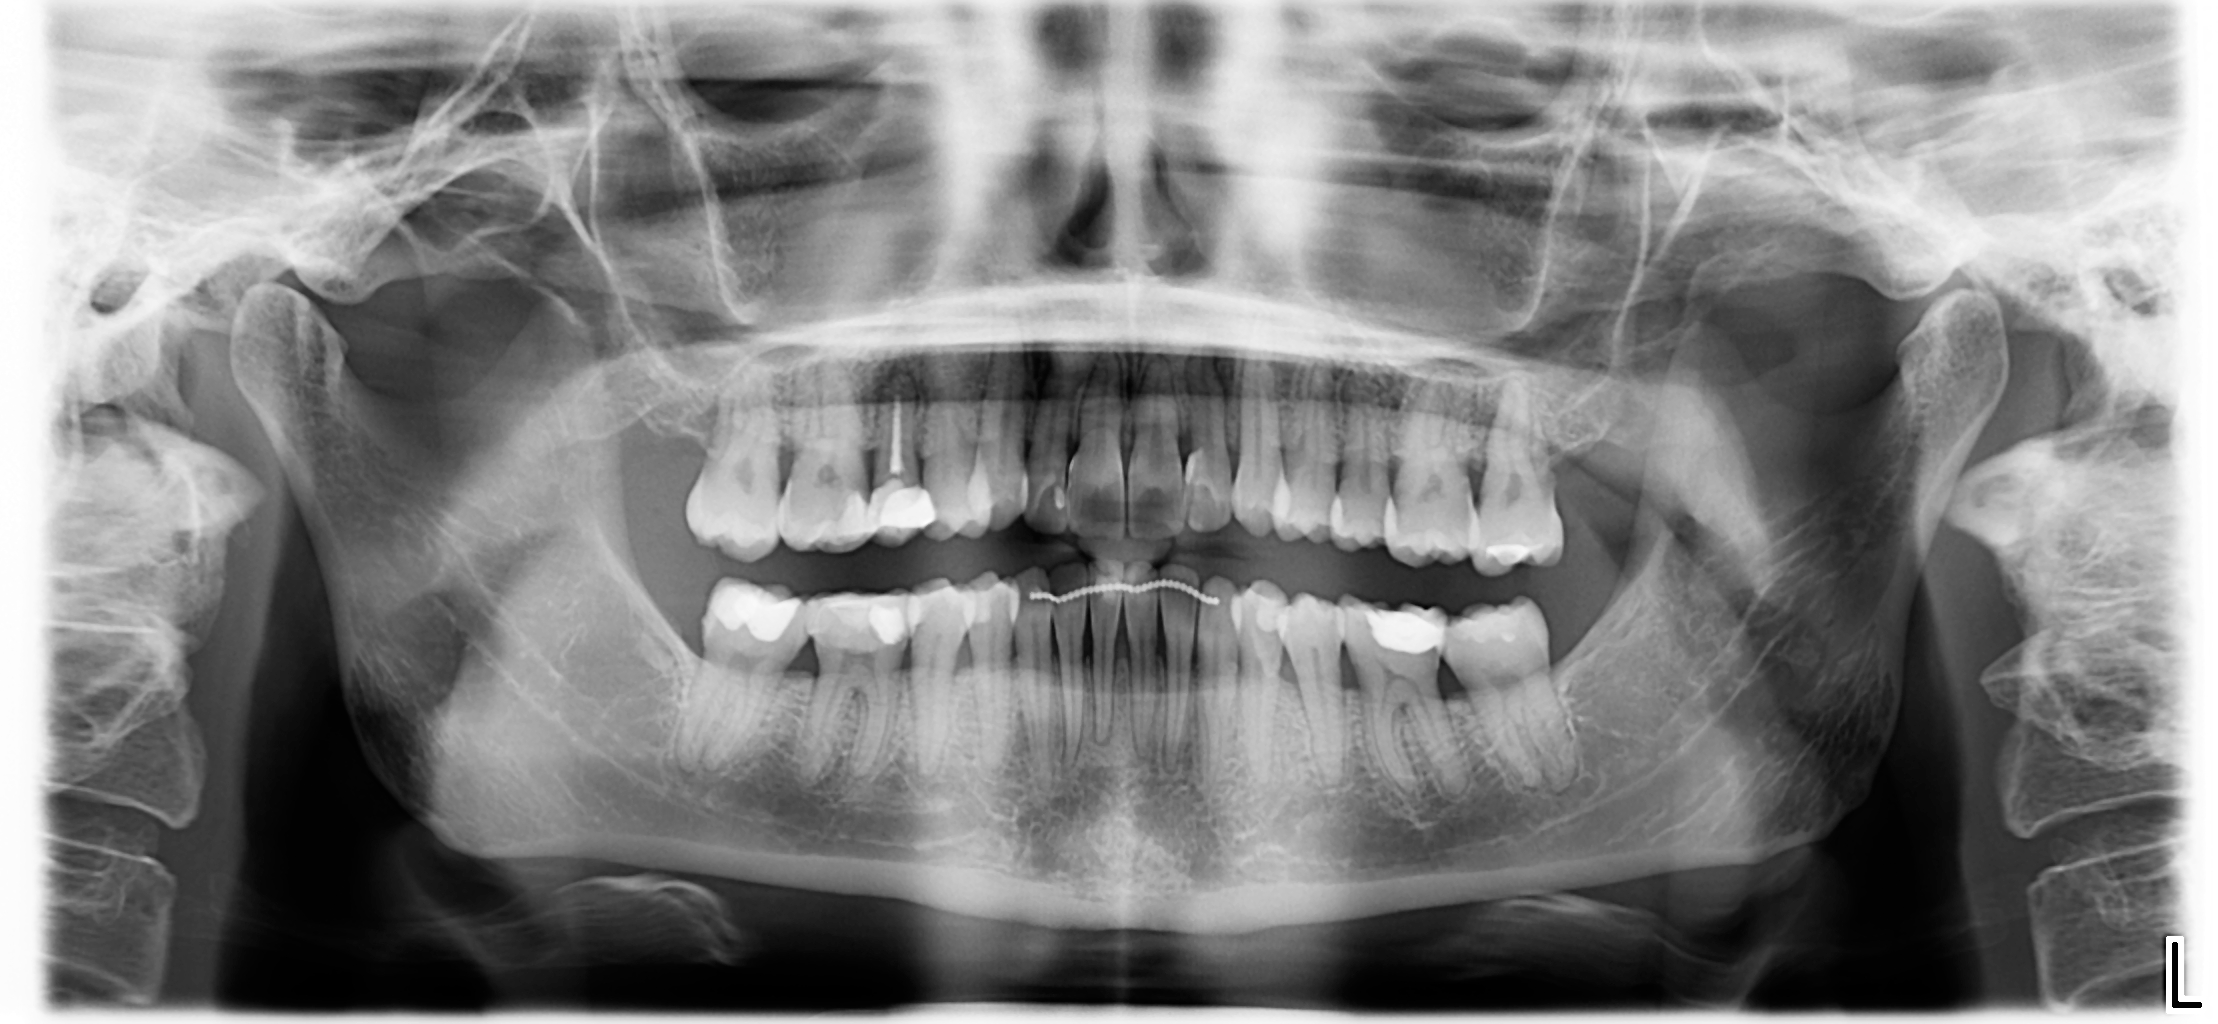

The patient, having completed a periodontal treatment phase, presented with significant aesthetic and functional concerns due to moderate crowding in both arches and a pronounced anterior crossbite. Clinical examination confirmed the need for comprehensive realignment, particularly in the anterior region. Although the patient had a history of periodontal issues, radiographic evaluation showed no signs of active disease. Based on these findings, the treatment plan was designed to carefully modulate orthodontic forces to protect the occlusion and surrounding tissues while addressing the misalignment.

At the conclusion of the treatment, the patient achieved excellent dental alignment and a stable occlusal relationship, particularly in the anterior region. Radiographs and clinical assessments confirmed that there was no further bone loss and that previous improvements were maintained. The aesthetic enhancement from the composite restorations further contributed to the overall success of the treatment.